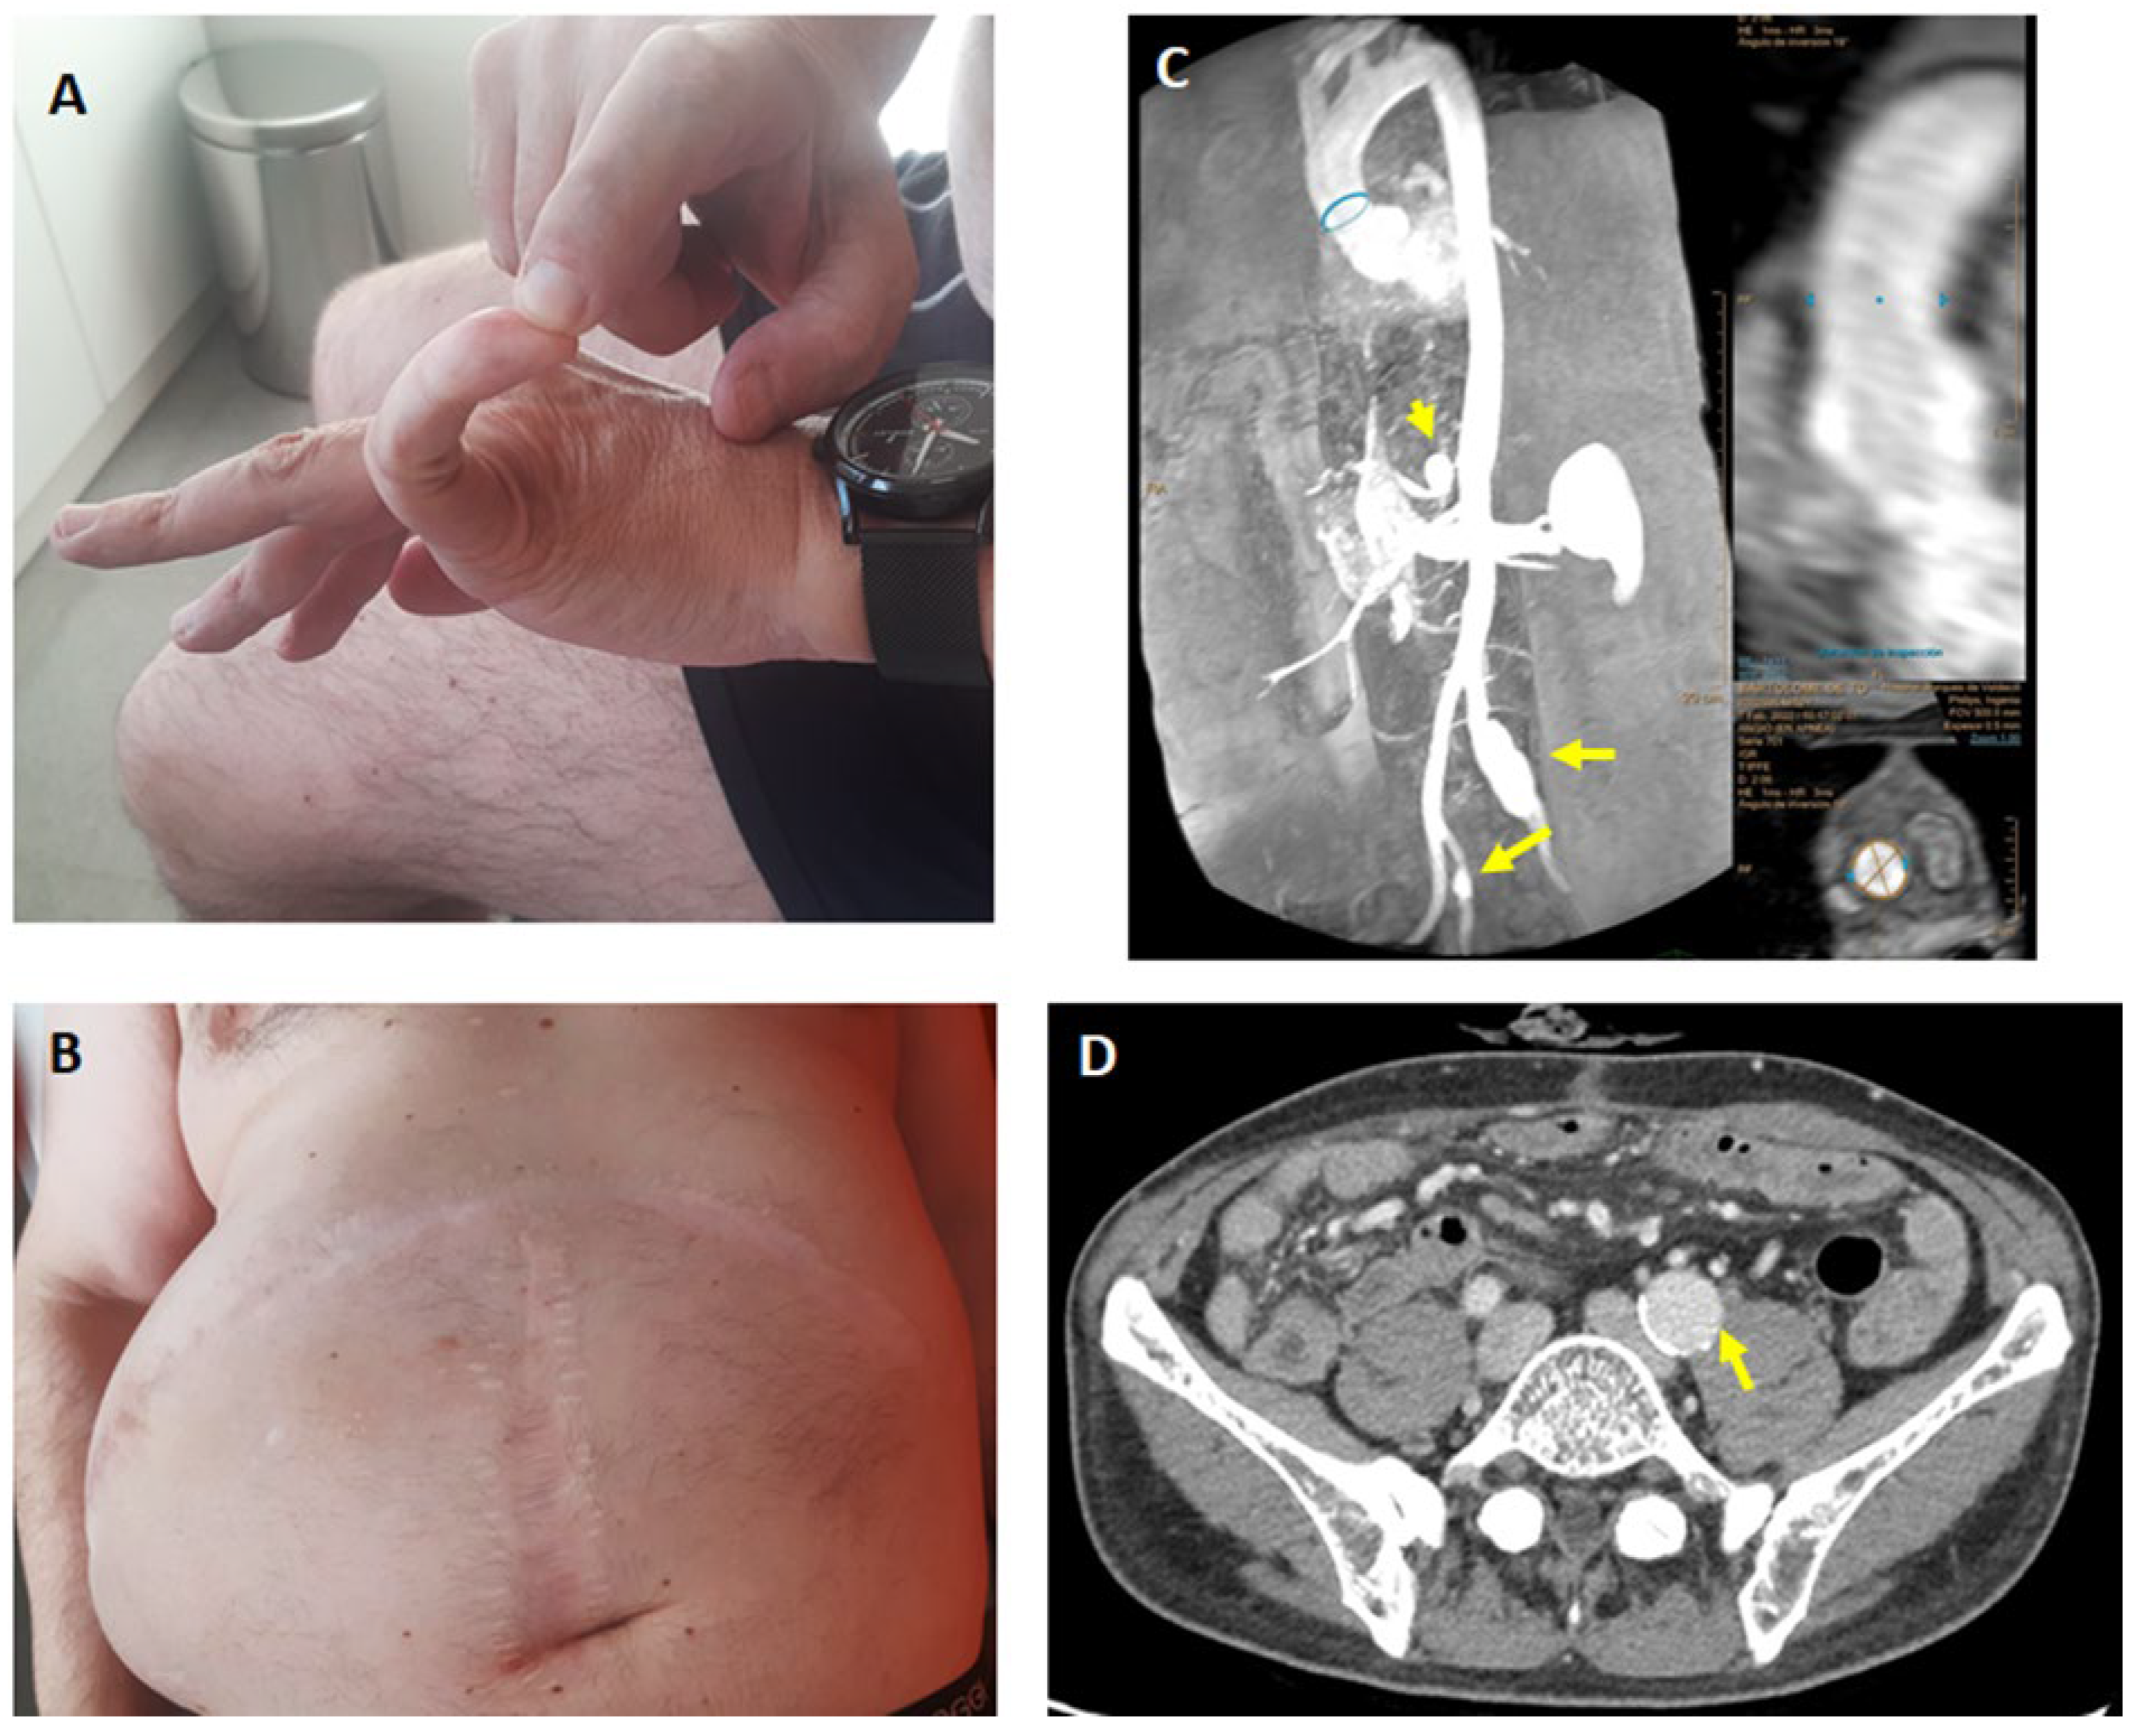

2.1. Clinical Data